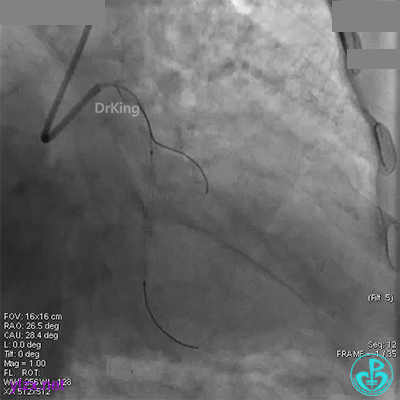

XB 3.0指引导管到位,导丝通过闭塞段至回旋支远段。

另一导丝保护分支,1.5×15mm球囊扩张闭塞处后造影,前向血流缓慢,远端分支血管没有充分显影。

1.5×15mm球囊扩张后前向血流缓慢的原因要高度怀疑慢血流。